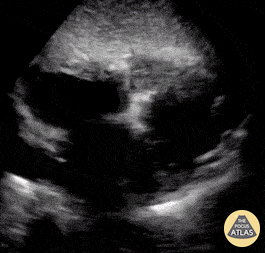

Normal Cardiac Anatomy - Normal subcostal view

Seen here is a normal subcostal view of the heart. Note the hyperechoic strings (chordae tendenae) attaching to the cusps of mitral and tricuspid valves as well as to the ventricular walls via the papillary muscles. There is also notable absence of any hypoechoic pericardial fluid or effusion. Shahad Al Chalaby, MD. PGY2, Internal Medicine Highland Hospital, Alameda Health System Internal Medicine Residency Program. CA, USA @shahad_Chalaby